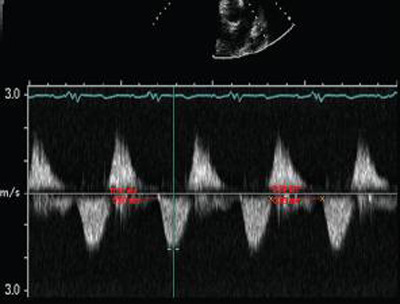

Doppler em um paciente com regurgitação pulmonar após reparo de tetralogia de Fallot. O paciente tem ventrículo direito não restritivo e onda "A" não é observada no espectro do Doppler de artéria pulmonar

De: Chaturvedi RR, Redington AN. Heart. 2007 Jul;93(7):880-9; usado com permissão